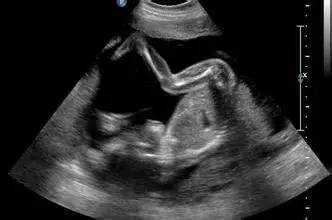

妊娠的11-14周胎儿的超声检查越来越重要,它筛查的临床意义在于以下几点:

1992年Nicolaides等研究发现大部分染色体异常胎儿在11-14周期间出现NT增厚现象。一项超过20万孕妇的前瞻性研究表明,NT可筛出超过75%有21三体和其他严重染色体异常的胎儿。至此以后,国内外陆续开始了11-14周胎儿的超声检查。

一、 胎儿染色体异常相关软标记筛查(遗传学超声检查)胎儿颈部透明层厚度(NT)

定义为胎儿颈后皮下组织内液体积聚的厚度。超声声像为颈后皮下组织内回声。首先头臀长的测量要求非常严格,有很多条件才能测得标准,从而核对好孕周。而NT测量技术也有这些标准:胎儿头臀长45-84mm;胎儿正中矢状面,自然弯曲;图像放至最大,只显示胎儿头部及上胸部;测量标尺轻微移动只改变结果0.1mm;测量皮肤与颈椎软组织间的最宽距离;测量三次,取最大值。如果测量不准确,就会出现假阳性。

NT测量结果的临床意义:NT的95百分位是2.5mm,大于等于3mm发生胎儿异常的可能性增加;NT增厚约10%合并胎儿染色体异常,最常见21三体综合征;NT越厚,染色体异常的风险越高;与胎儿畸形和不良妊娠结局密切相关,尤其先心病危险度为NT正常儿的6倍。